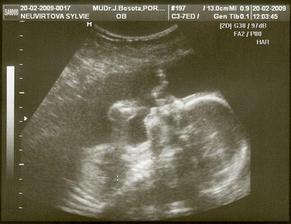

Tak zatím alespoň první fotečka našeho miláčka...

Seznámíme se spolu začátkem července🙂 ...

4.2.2009 19+3tt

Tak dneska jsme absolvovali druhý genetický UTZ, na kterém nám pan Dr.definitivně vyloučil NTD(rozštěpové vady, na které jsme měli zvýšené riziko z tripple testů)

Tak jsme si podruhé oddechli...10.2.nás čeká poslední genetický UTZ,tentokrát si na něj zajedem do Olomouce.Zjišťovali jsme zase pohlaví..ze začátku to byl kluk, na konci holčička, takže jsme tam, kde jsme byli..)